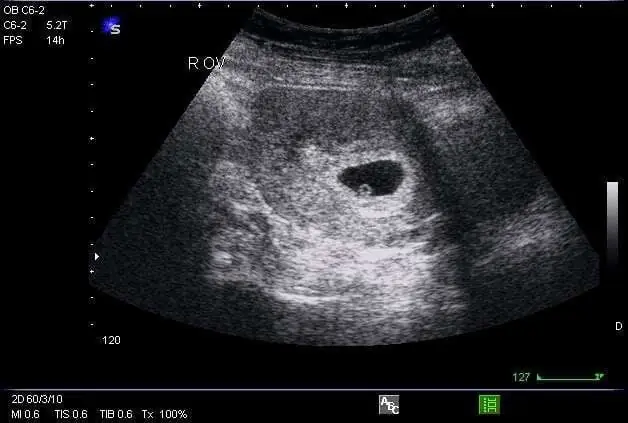

Siêu âm thai

Siêu âm là phương pháp chính xác để xác định phôi thai đã hình thành hay chưa. Tuy nhiên, siêu âm chỉ có thể nhìn thấy phôi thai rõ ràng sau khoảng 5-6 tuần tính từ ngày đầu tiên của kỳ kinh cuối cùng.